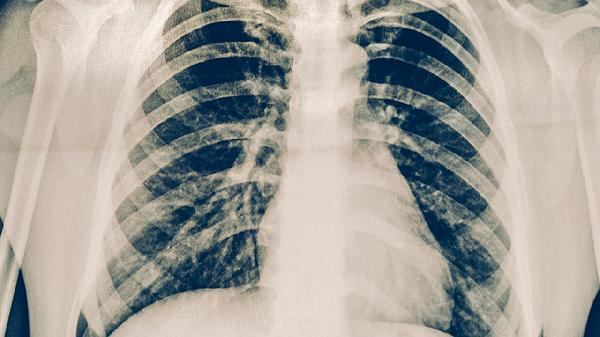

肺结核用药主要有异烟肼片、利福平胶囊、吡嗪酰胺片、乙胺丁醇片、链霉素注射液等。肺结核是由结核分枝杆菌感染引起的慢性传染病,需遵医嘱联合使用抗结核药物,全程规范治疗。

肺结核患者用药需严格遵循早期、联合、适量、规律、全程的原则,不可自行增减药量或停药。治疗期间应保持高蛋白、高维生素饮食,适当进行有氧运动增强体质。定期复查胸部影像学和痰菌检查,密切观察药物不良反应,出现视力模糊、皮肤黄染等症状需立即就医。保持居室通风良好,避免随地吐痰,咳嗽时用纸巾遮掩口鼻。